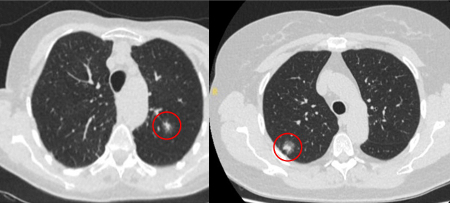

Computed tomography (CT) sections from two cases with benign perifissural nodules. Note the smooth margins and the normal undisturbed adjacent fissure

From the collection of Dr George Tsaknis, MD, PhD, FRCP(London), MRQA, MAcadMEd, PGCert; used with permission